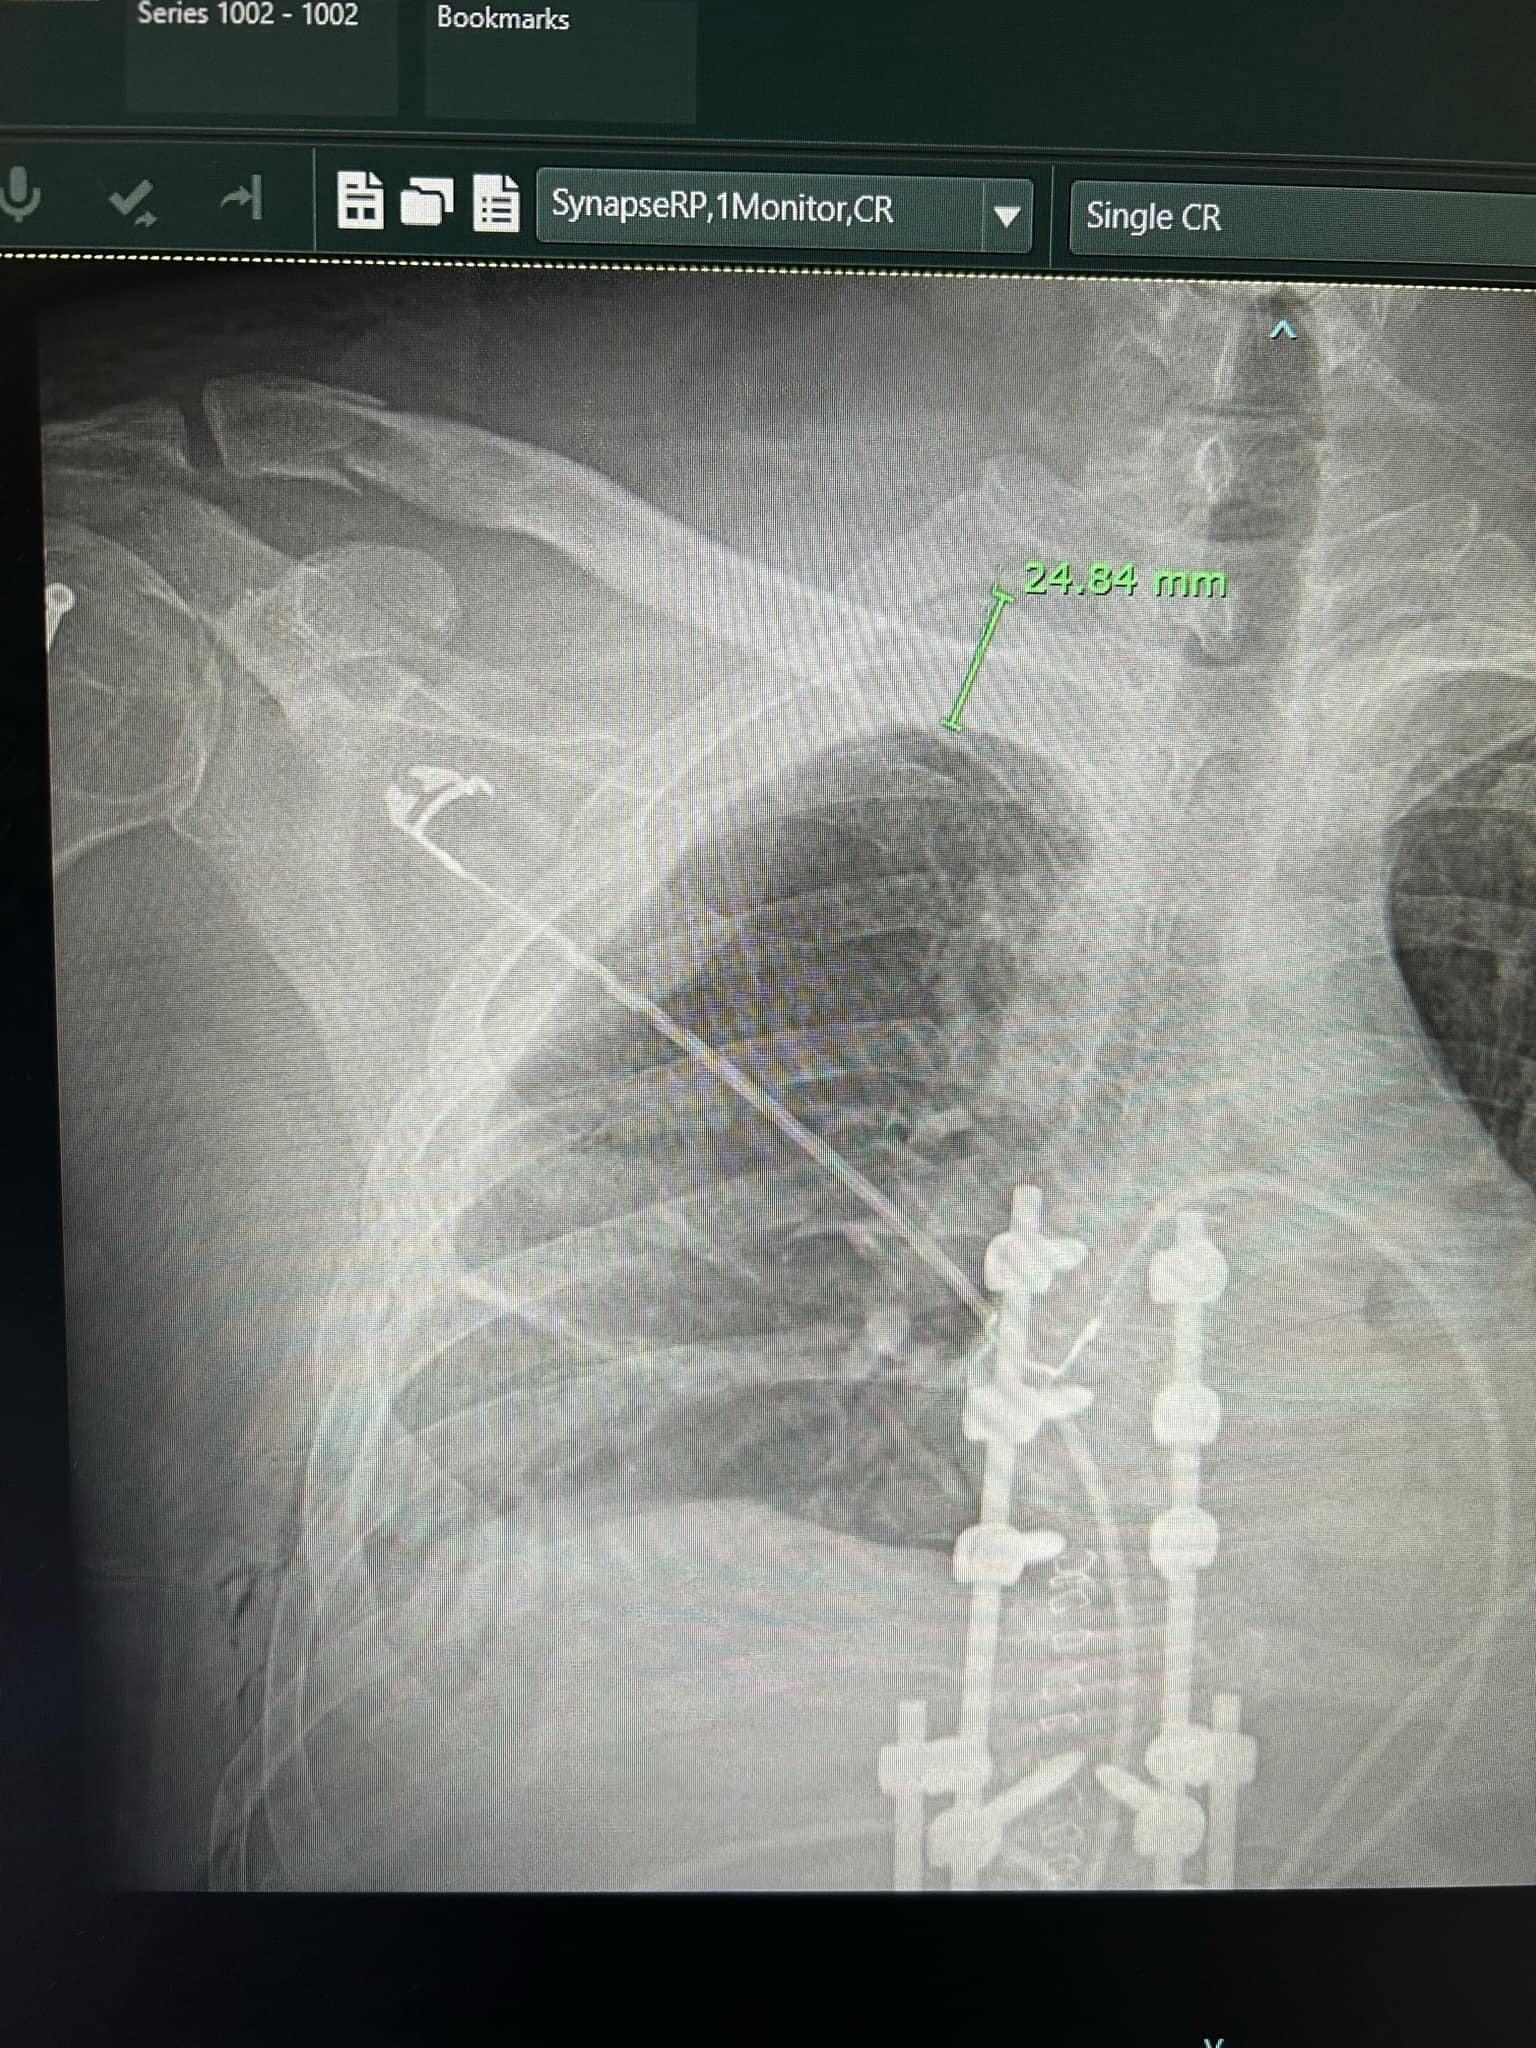

On April 28th, my partner Erick was in a serious mountain biking accident. He suffered a burst fracture in his spine (T1), a shoulder broken in three places, and eight fractured ribs. He’s already undergone emergency spinal surgery (a four-level fusion), and the recovery ahead will be long and intense—expected to take at four to six months, with physical therapy, follow-up scans, and a lot of healing time at home.